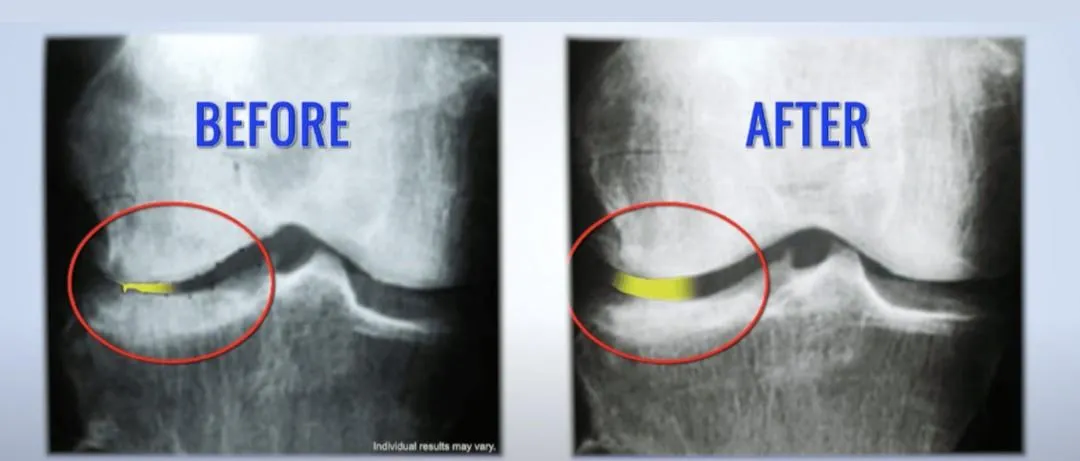

🔵 Degenerative or bone-on-bone joints